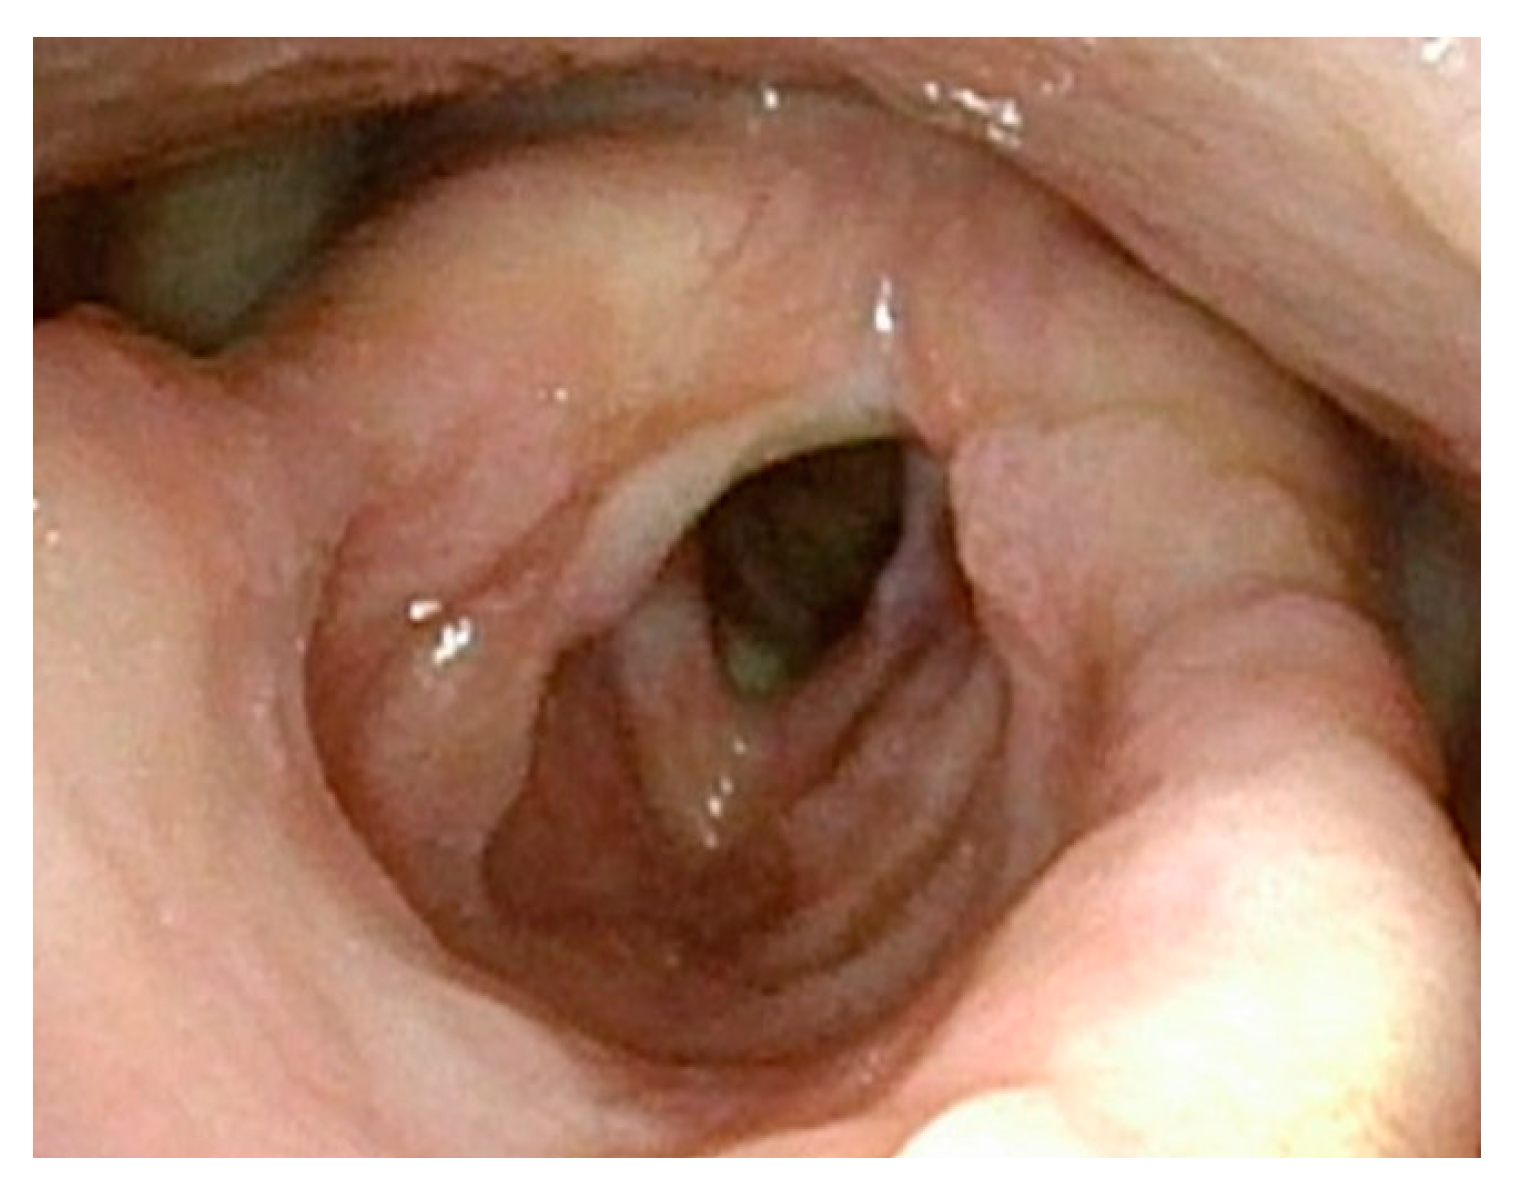

Figure 1 demonstrates a patient who had too aggressive anterior commissure laser treatment. A consequence of this was a very large anterior glottic web. Should this be encountered, the web may be lysed in the midline and steroid-injected (Figure 2). If the web is not the full thickness of the vocal folds, it should be cut with cold steel to help prevent the return of the web during healing. Once healed the web should be significantly improved (Figure 3). Consideration should be given to the dilation of the glottis following lysis.

Figure 3.

Three months post-op following laser ablation of laryngeal papilloma and lysis of anterior glottic web. The majority of the anterior glottic web is resolved, but there is already regrowth of papillomas.